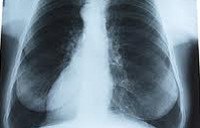

Рентгенография легких при серозном плеврите показывает гомогенное интенсивное затемнение в нижних отделах легочного поля; смещение границ сердца и средостения. Для уточнения серозного характера экссудата и природы заболевания выполняют плевральную пункцию (торакоцентез) с последующим цитологическим и биохимическим анализом плеврального выпота. В неясных диагностических случаях прибегают к пункционной биопсии плевры, диагностической торакоскопии или плевроскопии.